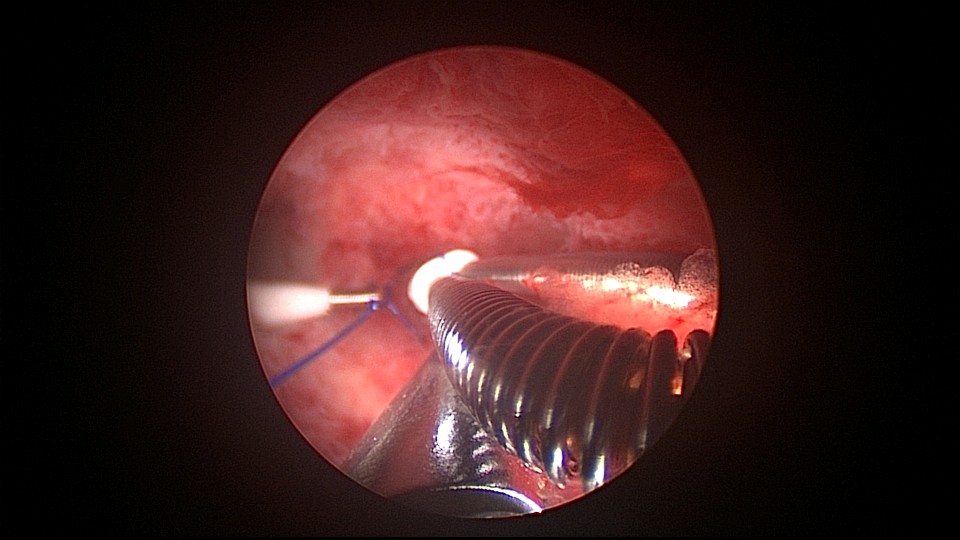

患者38岁,G5P1,剖宫产1次。2023年1月节育环下移带环受孕,宫腔镜取环终止妊娠,同时行左手上臂内侧皮埋避孕,遗憾的是手术医生术中没有找到节育环,术毕复查B超,环仍在宫腔,第二天宫腔镜探查,节育环位于切口憩室内,取出节育环。再次遗憾的是取环后阴道淋漓不净出血,术后第24天复查B超见胚物残留,第三次宫腔镜手术清除残留组织。2025年10月取出皮埋棒,2025年11月外院安环,术后2周复查B超环下移,2025年12月(月经干净3天后),安环医院取出节育环,取环后第6天到我院行宫腔镜安环并做节育环固定。子宫水平位,宫深8.5cm,见切口憩室比宫腔更宽大,形成类似金字塔形状(2次节育环下移原因),行宫腔镜下缝合线结固定节育环,打了3个结,拉过缝合点2个结。第十七例节育环固定。既往带环受孕,多次宫腔镜手术。术后2周复查B超,节育环位置正常,环顶端距宫底1.6cm。